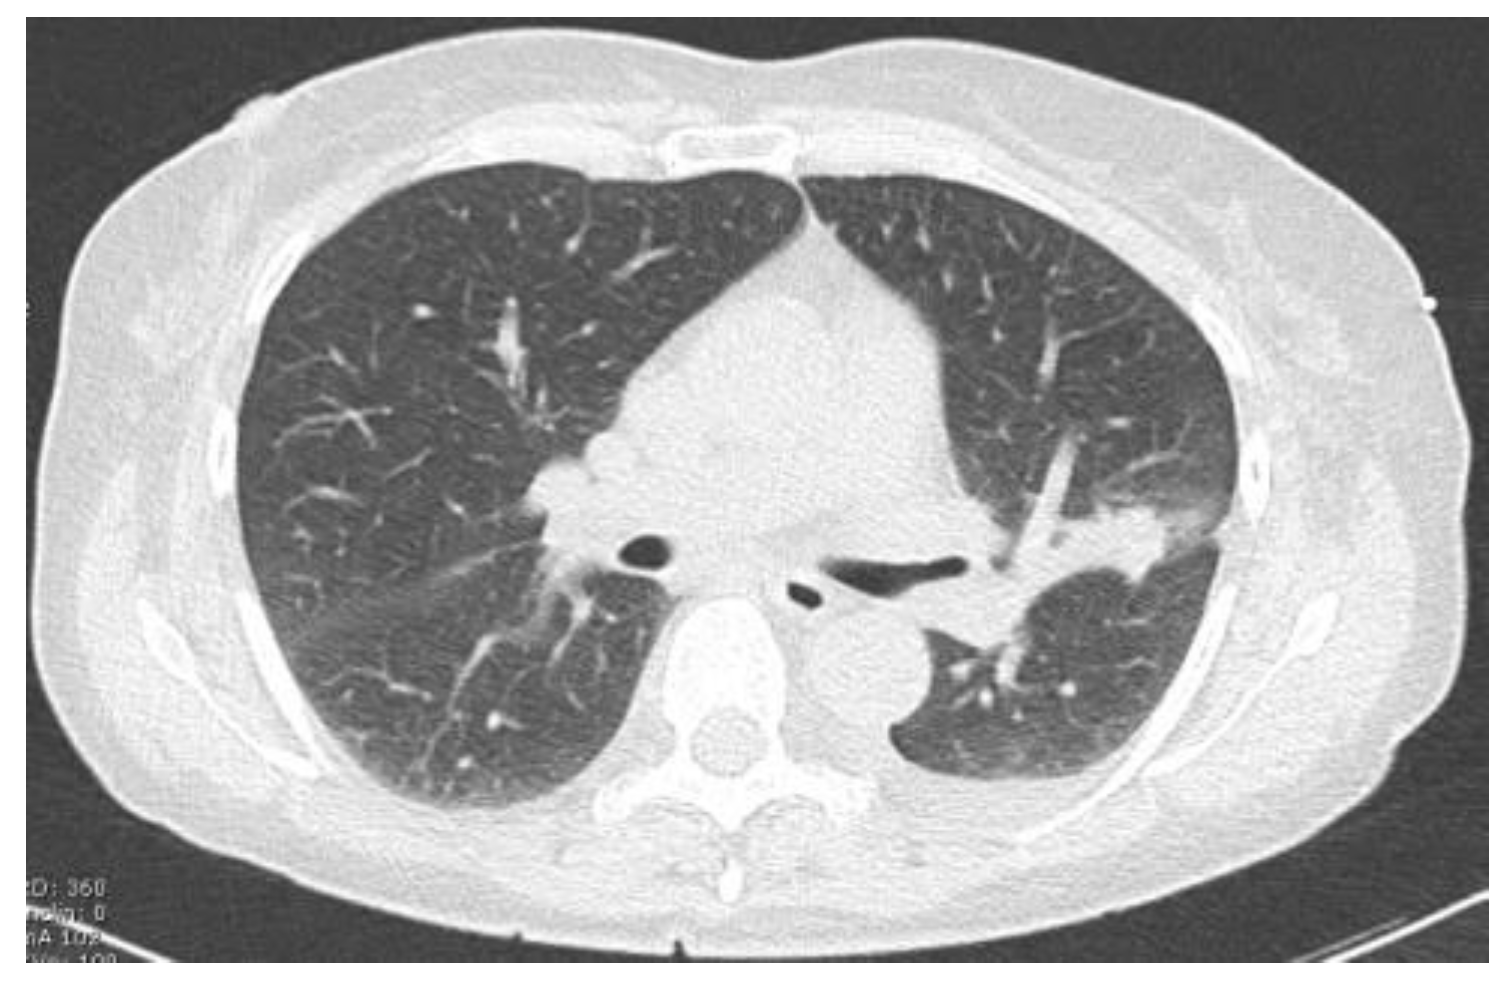

| Site of lung cancer | LUL | RLL | RUL | LLL | RUL | RUL | LUL | RUL |

| Clinical stage | IB | IB | IB | IA | IA | IB | IB | IB |

| Histotype | ADC | ADC | ADC | ADC | ADC | ADC | SCC | ADC |

| Site of Lung Cancer | Histotype | SPECT-Positive SLN Station | Intraoperative Positive SLN Station | |

|---|---|---|---|---|

| Patient 1 | LUL | ADC | 10 | 10 |

| Patient 2 | RLL | ADC | * | 9 |

| Patient 3 | RUL | ADC | 11 | 11 |

| Patient 4 | LLL | ADC | # | 11 |

| Patient 5 | RUL | ADC | # | 4 |

| Patient 6 | RUL | ADC | 10 | 10 |

| Patient 7 | LUL | SCC | * | 5 |

| Patient 8 | RUL | ADC | 10 | 10 |